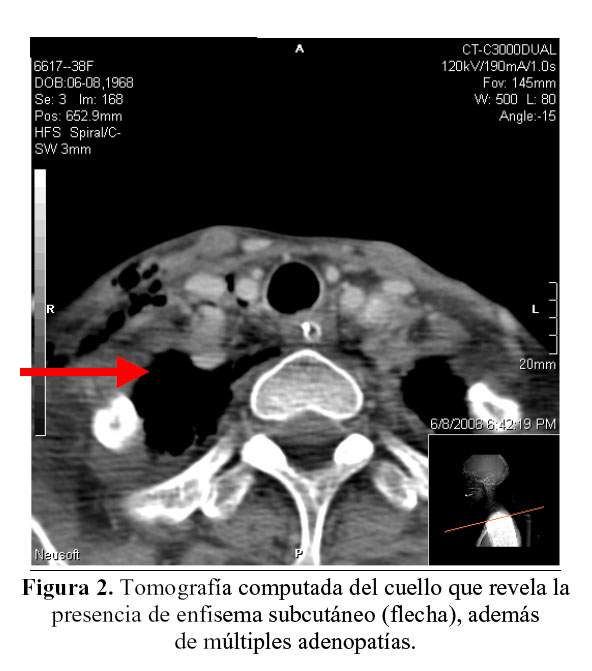

Las radiografías de esófago con doble contraste, revelaron abundante pasaje del contraste al árbol bronquial (Figura 1), indicando la presencia de una fístula probablemente con la tráquea. Además en la tomografía computada del cuello se observa la presencia de enfisema subcutáneo (Figura 2). Si bien la causa neoplásica más frecuente de fístulas tráqueo esofágicas es el cáncer de esófago (1), esta entidad produce esta complicación con poca frecuencia (2,3). También ocurren fístulas directas entre esófago y pulmón que son muy raras, así como fístulas esófago bronquiales; pero generalmente el cáncer de esófago se localiza en su tercio medio dando las fístulas traqueo-esofágicas.